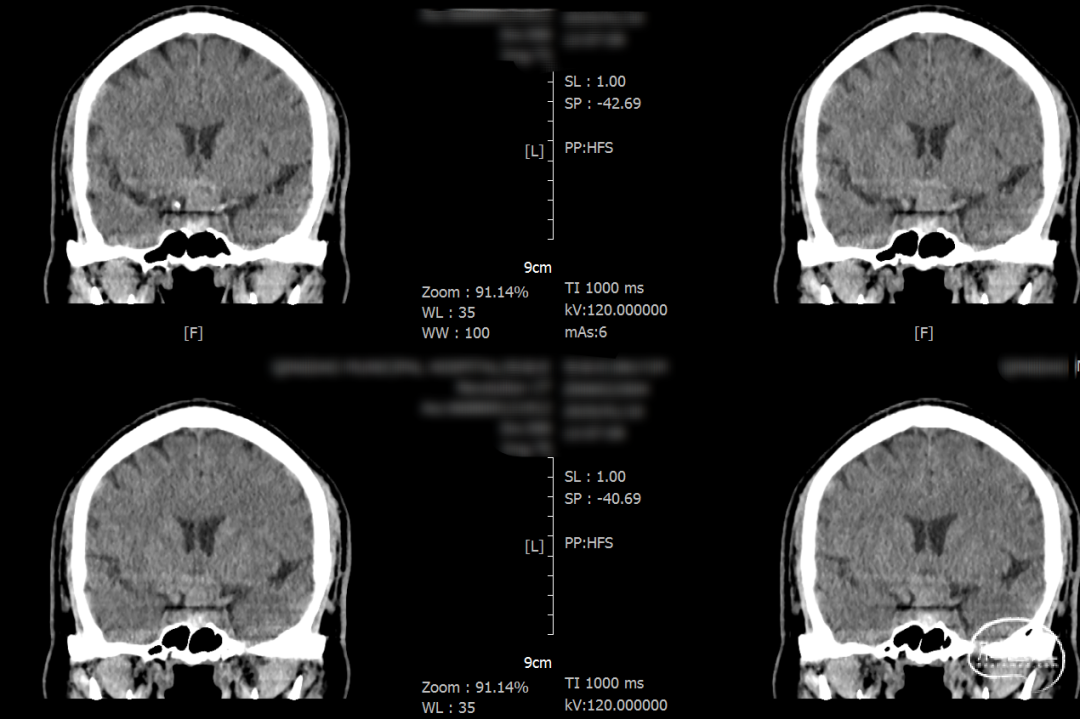

术后一天检查。